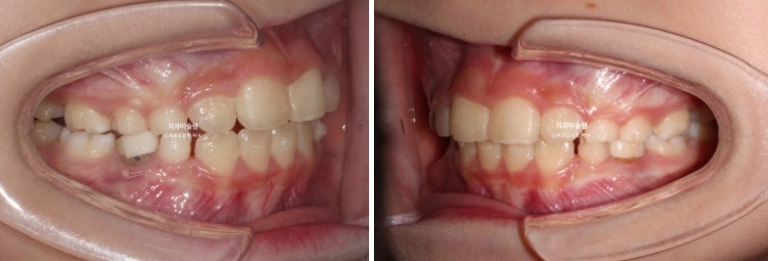

23.10~25.08